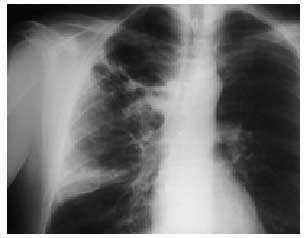

En las exploraciones complementarias destaca la presencia de leucocitosis con desviación izquierda e insuficiencia respiratoria hipoxémica. Los siguientes parámetros fueron compatibles con la normalidad: proteinograma, bioquímica, Mantoux, cultivo de esputo, serología de atípicas en primera determinación, coagulación y ECG. Se realizó una radiografía de tórax al ingreso (fig. 1). A su llegada a planta, y tras el diagnóstico de neumonía en el lóbulo superior derecho, se inicia tratamiento con claritromicina, quedando el enfermo apirético y con mejoría de la sintomatología que motivó el ingreso.

Fig. 1. Radiografía de tórax al ingreso.